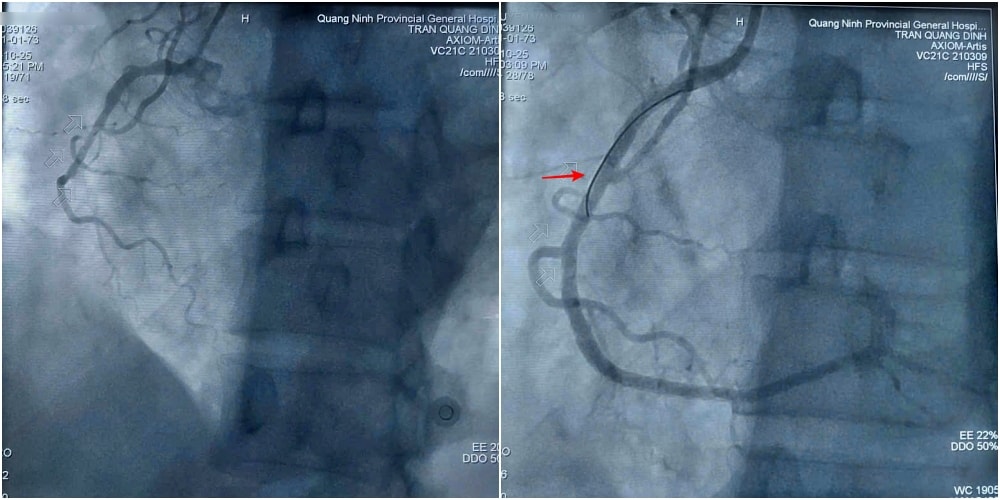

Sau khi hội chẩn và giải thích rõ tình trạng cho gia đình, ca bệnh được đội ngũ bác sĩ khoa Phẫu thuật và Can thiệp Tim mạch tiến hành khẩn trương. Kết quả chụp mạch cho thấy tổn thương nặng 3 thân động mạch vành, trong đó hẹp tắc hoàn toàn động mạch vành phải.

Kíp can thiệp tiến hành nong bóng và đặt 2 stent để tái thông động mạch bị hẹp tắc. Hình ảnh chụp kiểm tra sau thủ thuật cho thấy stent thông tốt, dẫn máu trở lại nuôi tim.